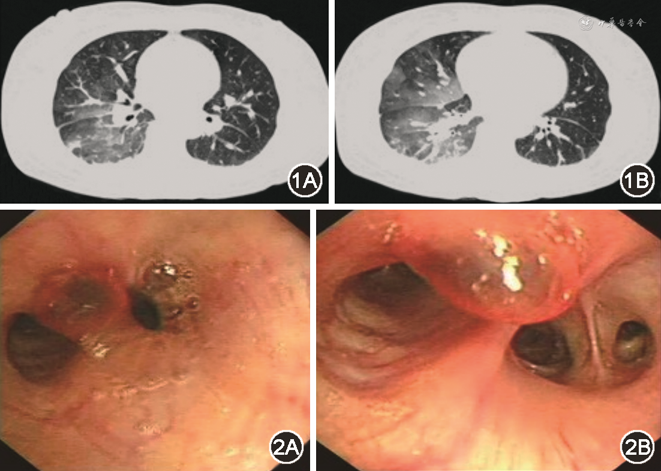

入院体格检查:体温36.8 ℃,脉搏62 次/min,呼吸20 次/min,血压179/92 mmHg(1 mmHg=0.133 kPa)。皮肤黏膜无瘀点瘀斑,呼吸平顺,右下肺可闻及少许湿啰音,心腹体查未见异常。血常规提示白细胞14.80×109/L,中性粒细胞百分比77.8%,红细胞2.84×1012/L,血红蛋白88 g/L,血小板197×109/L,D-二聚体(ELISA法)2 656 μg/L FEU,血气分析、凝血指标、肝肾功能、电解质、肺肿瘤指标、风湿免疫指标、真菌检查相关指标均正常。胸部支气管动脉+肺动脉增强CT提示两肺多发渗出病灶,以右下肺为著,考虑右肺多发肺泡积血,支气管管壁未见明显异常(图1A,1B),左下肺动脉外基底段轻度肺动脉栓塞,余肺动脉造影未见明确异常,两侧未见明确增粗支气管动脉。

支气管镜检查见气管、双侧支气管通畅,右中叶支气管开口处可见一暗红色结节,黏膜光滑,直径约2 mm,局部见陈旧性血迹,局部可见搏动(图2A,2B),此时考虑患者仍有活动性出血,量较大,未排除右中叶结节为血管病变,未予活检。